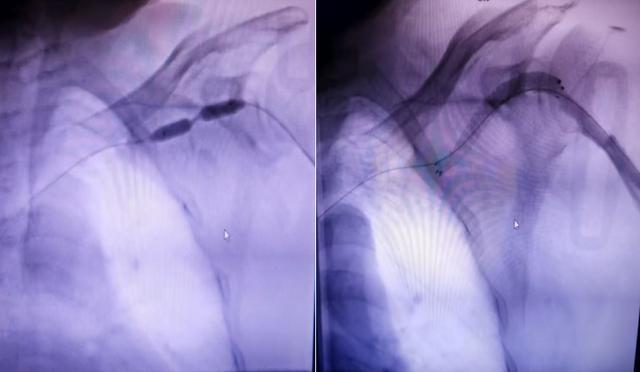

近日,怀化市中心医院(怀化市肿瘤医院)鹤城院区肾病内科团队为一名尿毒症内瘘闭塞患者,成功实施了DSA引导下PTA后Covera覆膜支架植入术。

DSA引导下PTA后Covera覆膜支架植入术

面对这一棘手难题,科主任陆小军主任医师带领血管通路团队仔细研讨评估后,为杨先生实施了一项更为先进的技术——PTA后Covera覆膜支架植入术。术后,杨先生立即恢复正常的血液透析,无并发症,内瘘震颤、搏动良好,并顺利度过围手术期,康复出院。